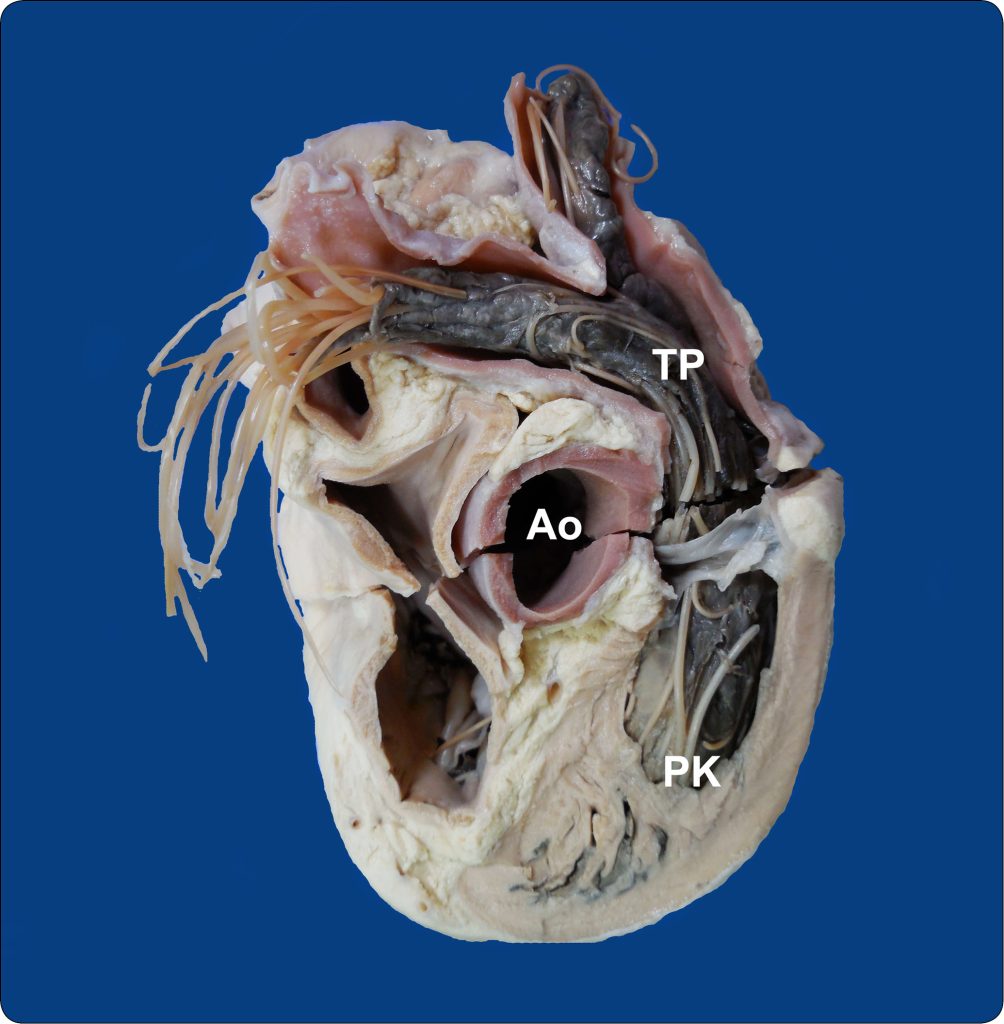

Nadciśnienie płucne może być wywołane zarówno obecnością pasożytów w prawej komorze serca i tętnicy płucnej (Dirofilaria immitis; ryc. 5), jak i w tkance płuc (nicienie płucne; ryc. 6). Ze względu na złożony mechanizm wywoływanych zmian infestacje pasożytnicze nie są zaliczane do typowo zapalnych przyczyn nadciśnienia płucnego (typ 3) (2). Obecność pasożytów może skutkować zapaleniem drobnych tętniczek płucnych, epizodami zatorowo-zakrzepowymi, a także cechami zapalenia płuc (2). Ten typ nadciśnienia płucnego jest wyjątkowy w medycynie weterynaryjnej, jako że ludzie nie są narażeni na rozwój PH w efekcie obecności Dirofilaria immitis czy Angiostrongylus sp. (2).